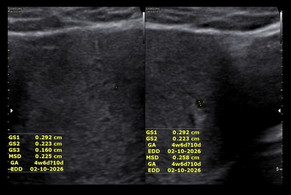

ขอเล่าก่อนนะคะ คือมี ปจด ครั้งล่าสุด 3 ธันวา แล้ววันที่ 30 ธันวาก็มีมาอีก คือ งง ว่าทำไมเดือนเดียวมาสองครั้ง ? เลยไม่มั่นใจว่าควรนับอายุครรภ์ยังไงค่ะ แล้วประมาณวันที่ 20 กว่ามกรา รู้สึกหน่วงท้อง ปวดท้องน้อยเหมือน ปจด จะมาอยู่หลายวันมาก จนเมื่อวานเอะใจเลยซื้อที่ตรวจมาตรวจ ตรวจตอนเย็นสรุปคือขึ้น 2ขีด แบบรวดเร็วไม่ทันตั้งตัว เลยคิดว่าคงผิดมั้ง เลยตรวจเช้านี้ดูค่ะ ได้ตามที่เห็นในภาพเลย ถ้าตรวจแล้วขึ้นแบบนี้ควรไปหาหมอเลยไหมคะ เมื่อปี 66 เคยมีประสบการณ์ตั้งครรภ์ ประมาณ 4สัปดาห์ แต่น้องหลุดไปแบบธรรมชาติ #ขอคำแนะคำปรึกษาคะ #ท้องแรก